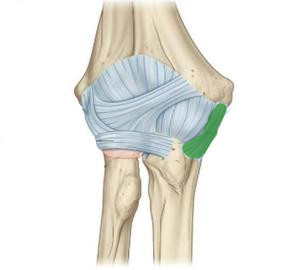

What is this structure?

Annular ligament of the elbow